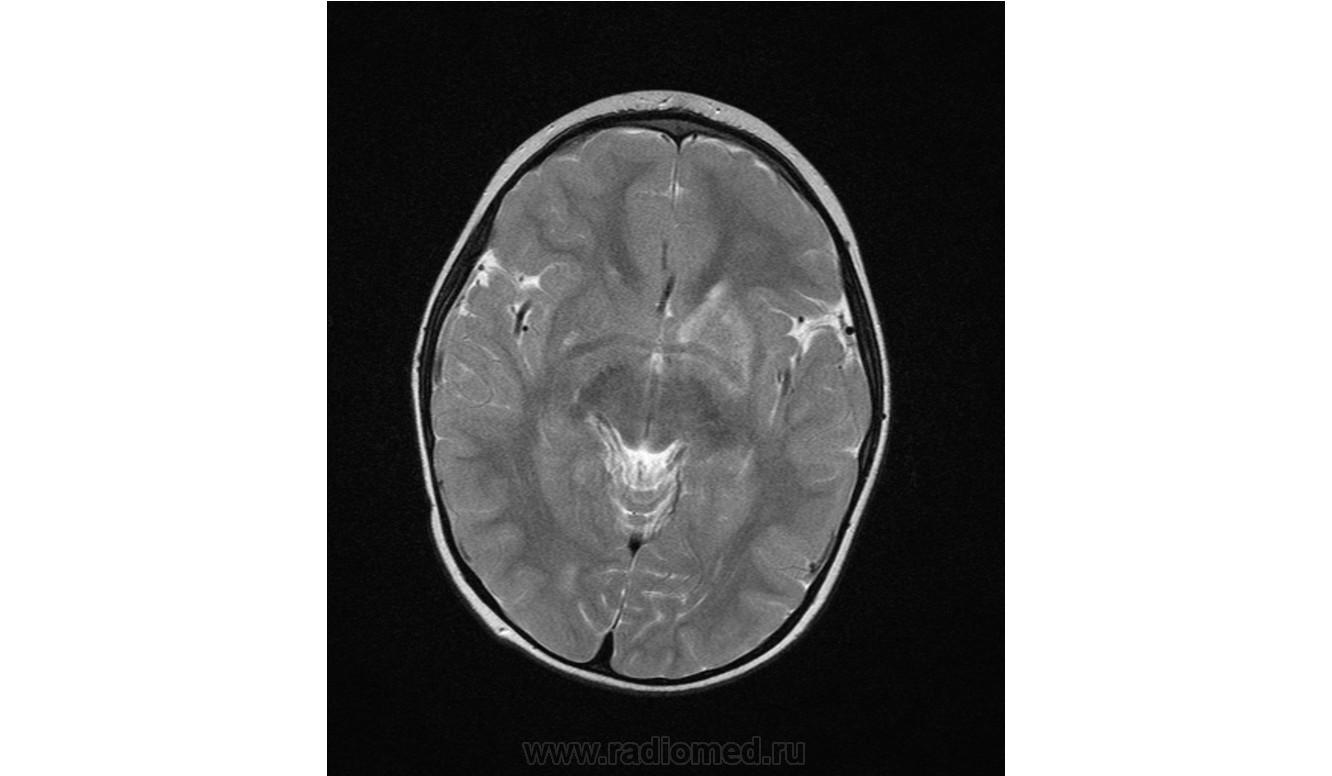

Помогите пожалуйста при постановке диагноза

Ребенок 2 года, заболели в середине декабре, гемипорез, к сожелению не могу ни как с контрасном исследованеим здесь загрузить но накапление контрасного вещества нет, спосибо за помочь!!!!!!!

Предположу гипоксически-ишемические изменения с диапедезным кровоизлиянием. Но они чаще двусторонние.